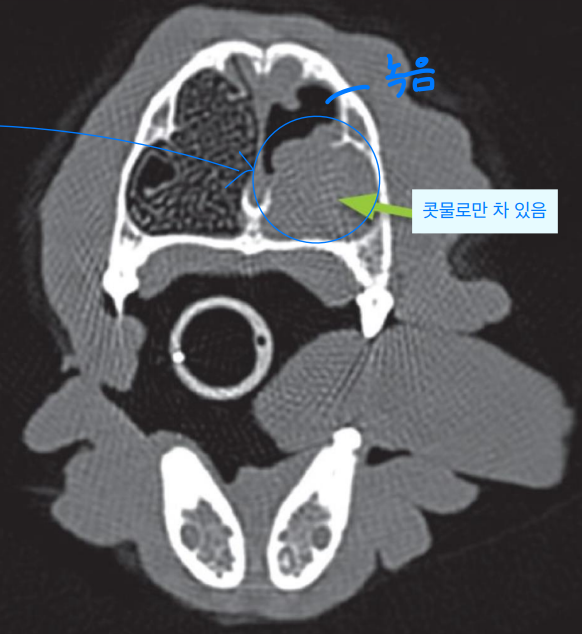

- 영상 진단 : well-defined lucent areas (조직이 녹아 어둡게 보임)

- 비경 검사(Rhinoscophic abnormalities) : nasal turbinate의 erosion, fungal plaques (white-to-green)

- turbinate, vomer, facial bone의 destruction이 관찰될 때

- CT, MRI가 radiography보다 빠르고 정확하다. 추천!